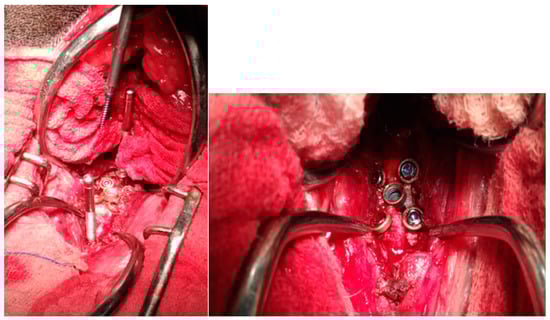

2.2. Surgical Technique